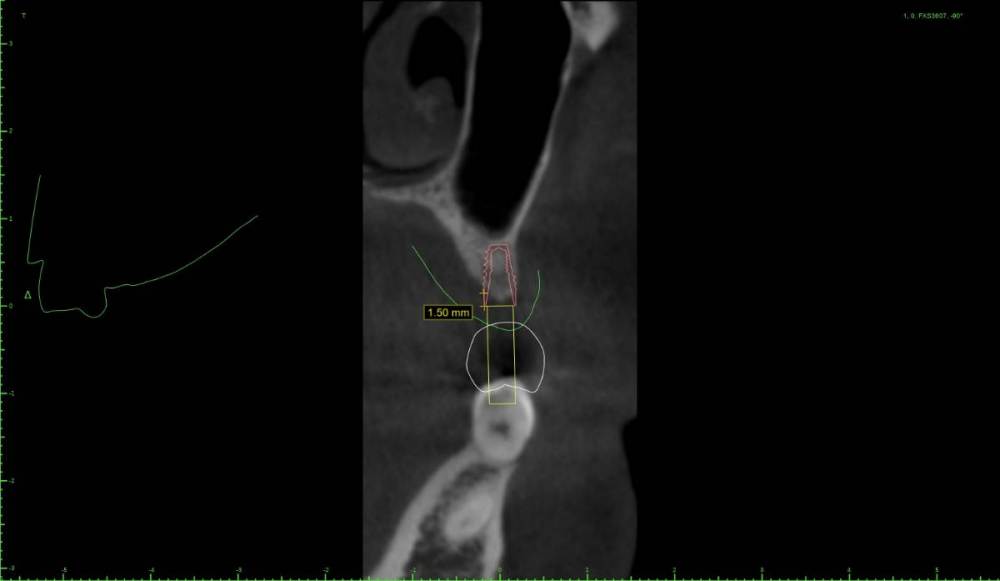

Женька Опубликовано 22 мая, 2021 Поделиться Опубликовано 22 мая, 2021 Дабы не захламлять тему про "мильён вопросов" я всё же создал свою. Итак, я получил оттиск верхней челюсти, отлил модель и перевёл в stl. Мои остеотомы застряли где-то в Пуяне и постучать нечем. Но в теме с мильёном вопросов пришли к выводу, что и зсл не нужен, только нкр. Что под рукой: даск с его фрезами для зсл, мембрана еволюшн, микс апатоса и только нитки, чтобы всё это зафиксировать. Также есть вариация имплантата суперлайн 2 (1.5мм полированной шейки и 5.5 шероховатой) или же полностью шероховатый суперлайн 1 с полированной фаской (3.6*7мм), но макродизайн менее агрессивный. Также будет сделан шаблон под пилотное сверление. Вот такие варианты получились. Вопрос, можно ли будет сделать маленькую нкр с имплантатом имеющим 1.5мм полированную шейку (как я понимаю - нет)? Ссылка на комментарий

Женька Опубликовано 3 июня, 2021 Автор Поделиться Опубликовано 3 июня, 2021 @Bier позицию бы выбрали иначе, чем на снимках? Ссылка на комментарий

Bier Опубликовано 3 июня, 2021 Поделиться Опубликовано 3 июня, 2021 да, разумеется. ставил бы по кости. Ссылка на комментарий

Женька Опубликовано 3 июня, 2021 Автор Поделиться Опубликовано 3 июня, 2021 @Bier Олег Юрьевич, не могли бы вы нарисовать, пожалуйста как и куда. Имплантат 3.5 минимальный диаметр возможный... и либо 7 либо 8 мм. Ссылка на комментарий